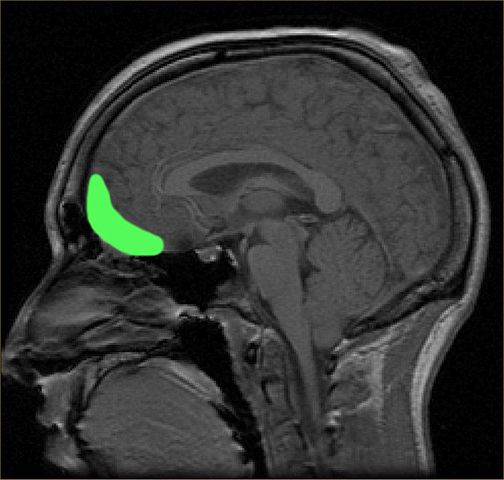

Que nous dit la science sur le contrôle de soi ? A quelles règles est-il soumis ? Comment ce contrôle de soi peut-il s’affaiblir ? Comment développer ses capacités de contrôle de soi ? Comprendre les mécanismes de l’auto-régulation et du contrôle de soi, c’est comprendre le fonctionnement du